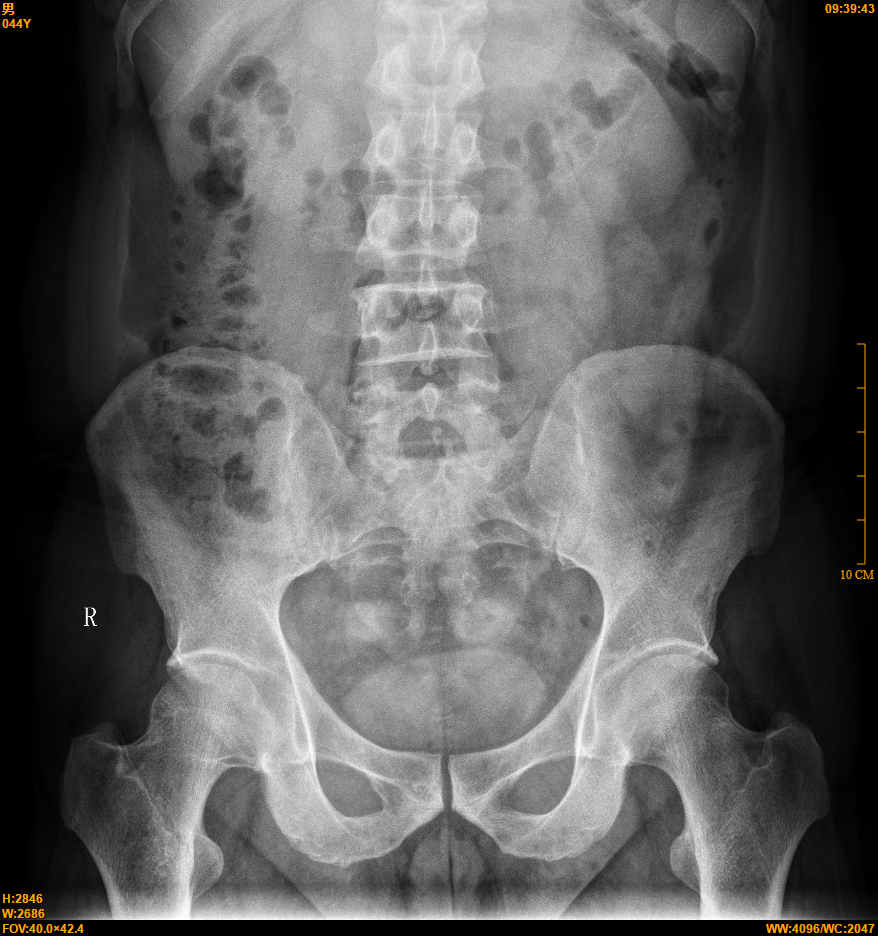

【影像】X线报骨盆未见骨关节异常,腰椎向左侧弯。